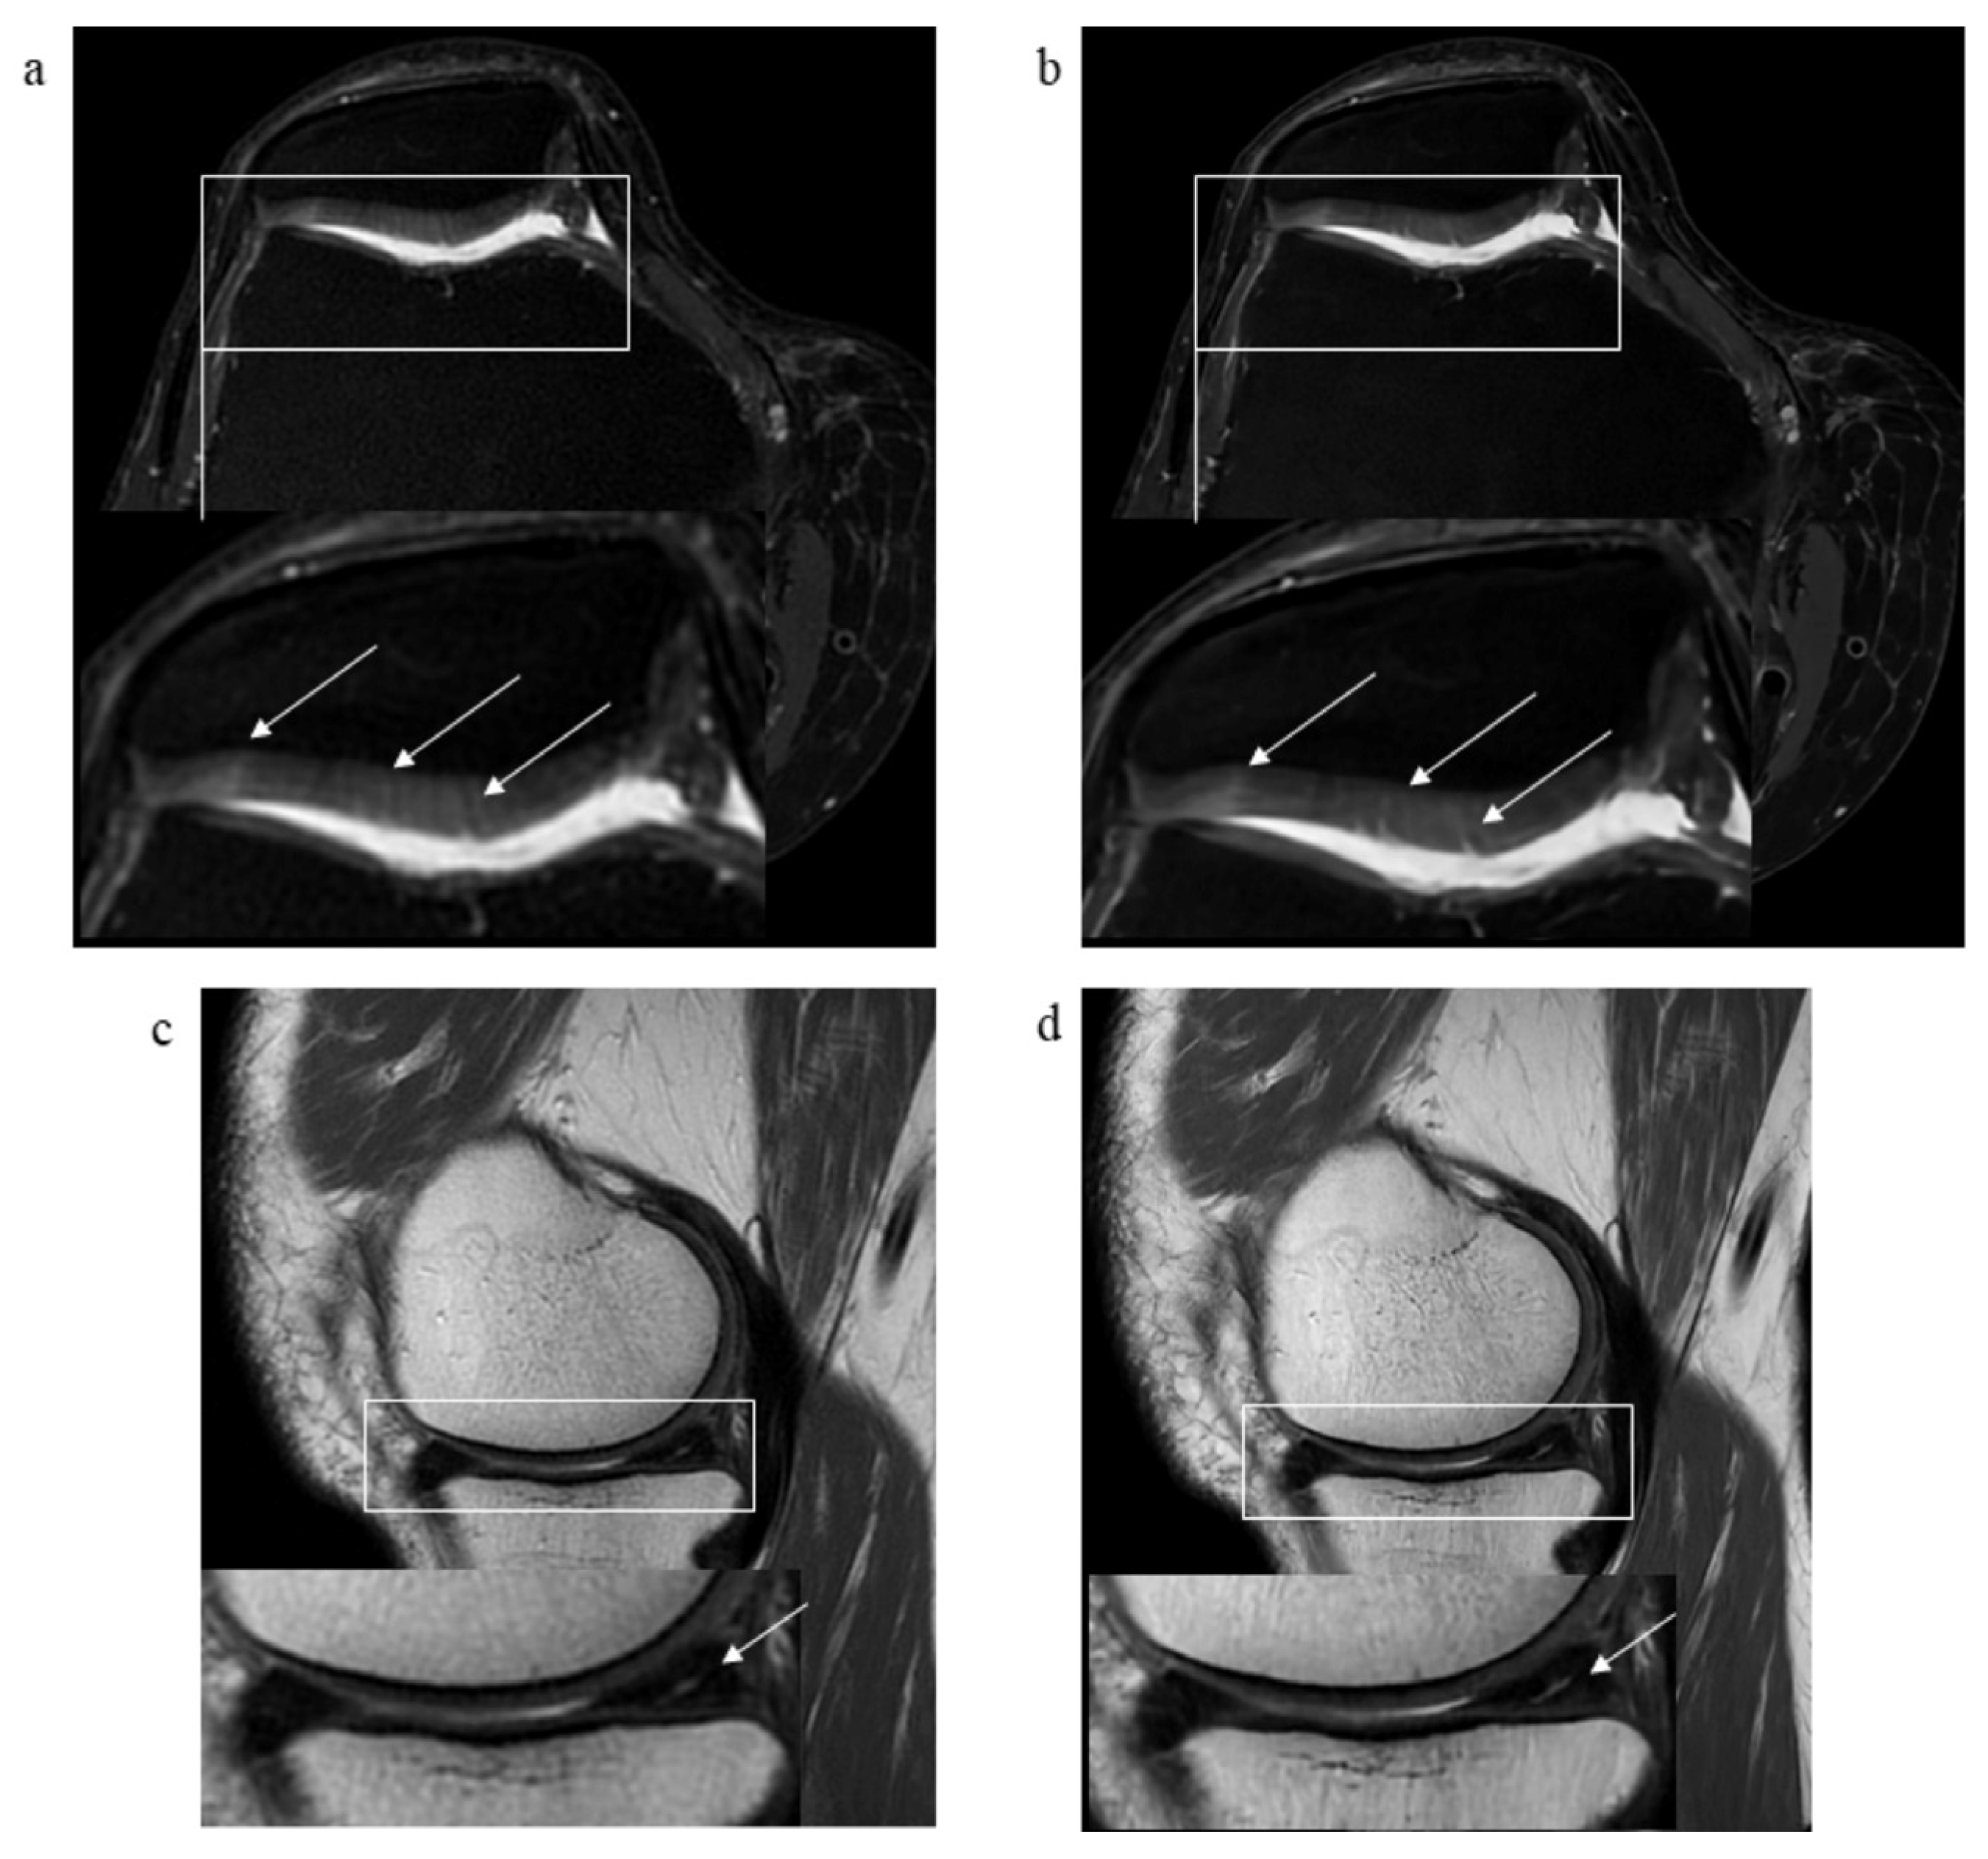

3.2. Pathological Findings